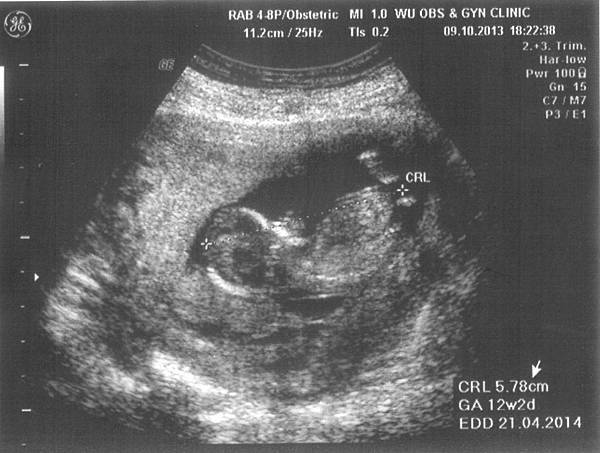

14w0d-116w6d-115w2d-115w2d-216w6d-1